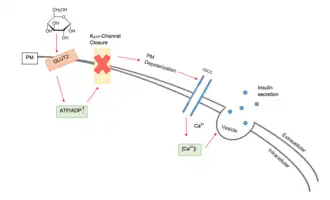

Insulin secretion

In beta cells, insulin release is stimulated primarily by glucose present in the blood.[4] As circulating glucose levels rise, such as after ingesting a meal, insulin is secreted in a dose-dependent fashion.[4] This system of release is commonly referred to as glucose-stimulated insulin secretion (GSIS).[10] There are four key events to the triggering pathway of GSIS: GLUT dependent glucose uptake, glucose metabolism, KATP channel closure, and the opening of voltage gated calcium channels causing insulin granule fusion and exocytosis.[11][12]

Voltage-gated calcium channels and ATP-sensitive potassium ion channels (KATP channels) are embedded in the plasma membrane of beta cells.[12][13] Under non-glucose stimulated conditions, the KATP channels are open and the voltage gated calcium channels are closed.[4][14] Via the KATP channels, potassium ions move out of the cell, down their concentration gradient, making the inside of the cell more negative with respect to the outside (as potassium ions carry a positive charge).[4] At rest, this creates a potential difference across the cell surface membrane of -70mV.[15]

When the glucose concentration outside the cell is high, glucose molecules move into the cell by facilitated diffusion, down its concentration gradient through glucose transporters (GLUT).[16] Rodent beta cells primarily express the GLUT2 isoform, whereas human beta cells, although also expressing GLUT2, mainly make use of GLUT1 and GLUT3 isoforms.[17][18] Since beta cells use glucokinase to catalyze the first step of glycolysis, metabolism only occurs around physiological blood glucose levels and above.[4] Metabolism of glucose produces ATP, which increases the ATP to ADP ratio.[19]

The KATP channels close when the ATP to ADP ratio rises.[13] The closure of the KATP channels causes the outward potassium ion current to diminish, leading to inward currents of potassium ions dominating.[14] As a result, the potential difference across the membrane becomes more positive (as potassium ions accumulate inside the cell).[15] This change in potential difference opens the voltage-gated calcium channels, which allows calcium ions from outside the cell to move into the cell down their concentration gradient.[15] When the calcium ions enter the cell, they cause vesicles containing insulin to move to, and fuse with, the cell surface membrane, releasing insulin by exocytosis into the pancreatic capillaries.[20][21][22] The venous blood then eventually empties into the hepatic portal vein.[22]

- Sulfonylureas are insulin secretagogues that act by closing the ATP-sensitive potassium channels, thereby causing insulin release.[35][36] These drugs are known to cause hypoglycemia and can lead to beta-cell failure due to overstimulation.[2] Second-generation versions of sulfonylureas are shorter acting and less likely to cause hypoglycemia.[36]